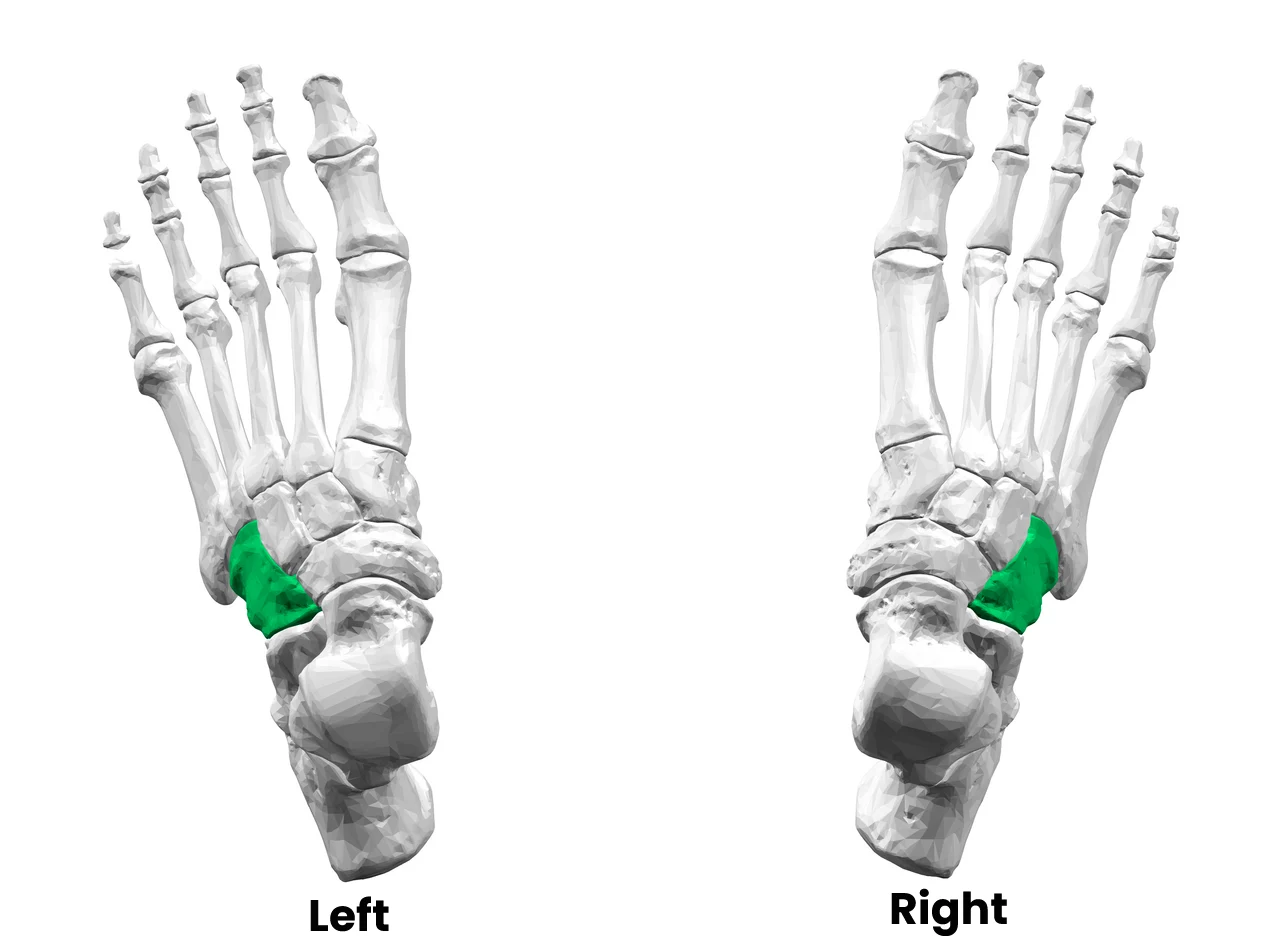

Location

The cuboid bone is located on the lateral (outer) side of the foot. It sits between the calcaneus (heel bone) and the bases of the fourth and fifth metatarsal bones. This position makes it an important structural link between the rearfoot and the forefoot.

Articulations

The cuboid forms several important joints. Most notably, it articulates with the calcaneus at the calcaneocuboid joint, which plays a key role in foot mobility and stability. It also connects with the fourth and fifth metatarsals, contributing to the function and flexibility of the lateral column of the foot.